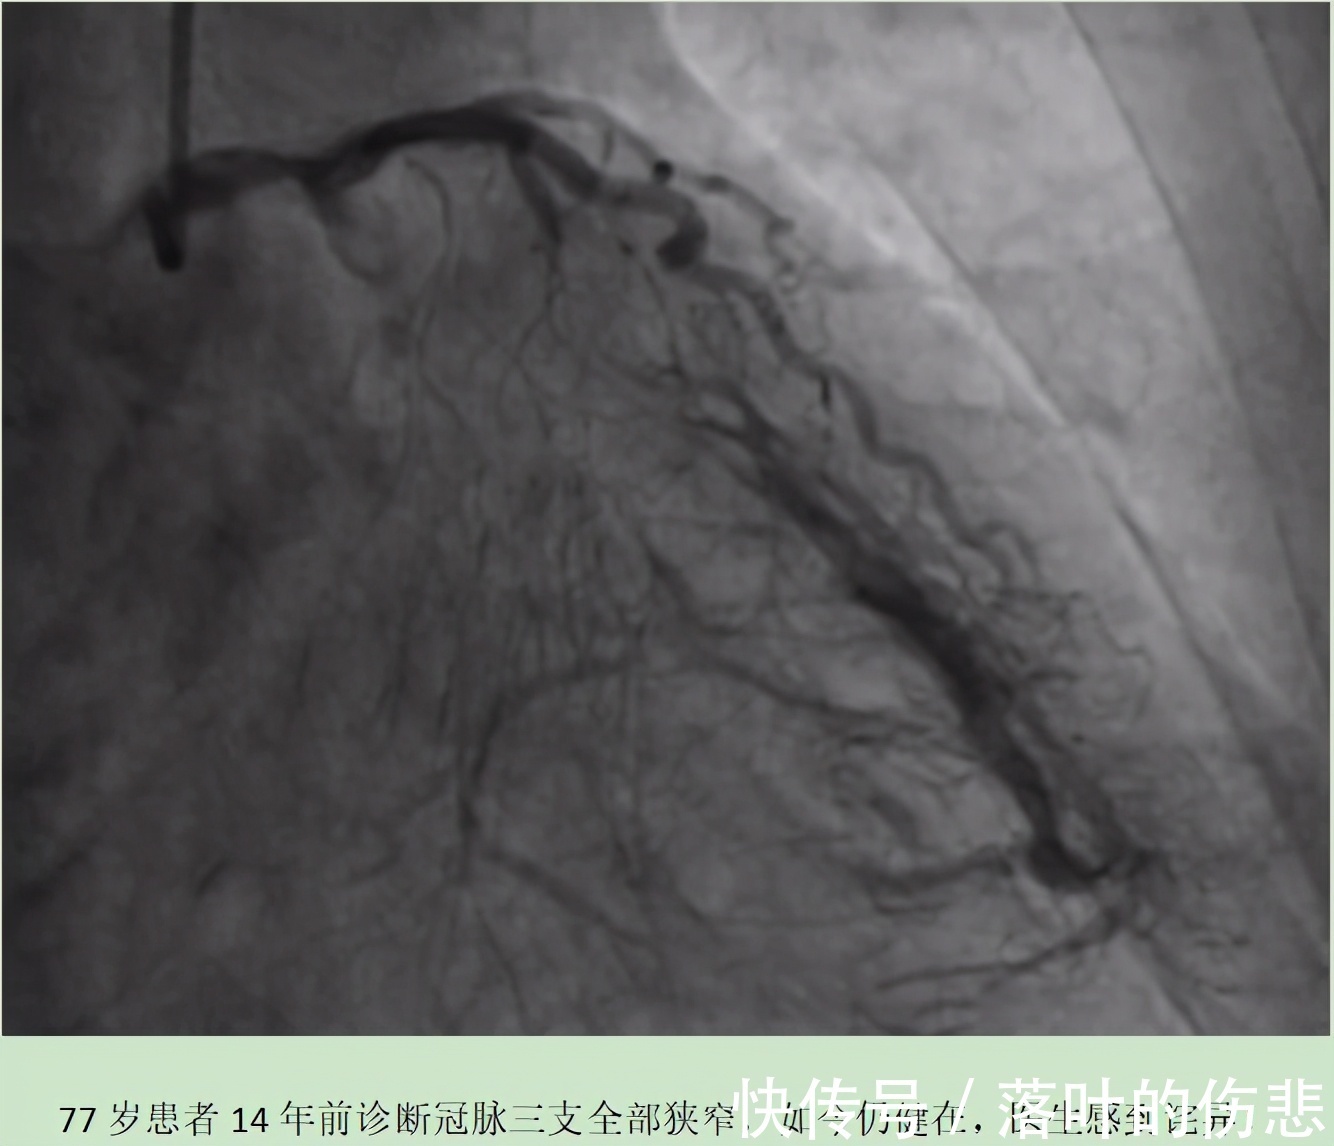

事实证明,老马说的全都是真的。因为在后来一次复查时,老马做了冠脉造影检查,结果发现他的冠状动脉三支仍存在进展性狭窄病变。只不过,在三支主血管的周围也生出了庞大的分支系统,有些分支血管足够强大,甚至超过了主血管。简单来说,老马的心脏成功建立了侧支循环。所以,在负责心脏供血的冠状动脉被堵时,侧支循环就开始发力,并取而代之,成为心脏供血供氧的主力。这或许就是老马能健康地活到现在的主要原因。